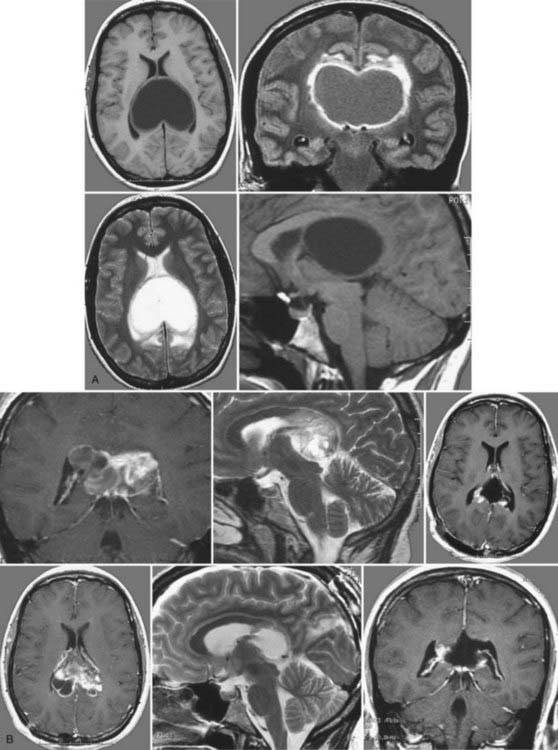

研究采用自2002年以来治疗的27例丘脑肿瘤患儿。其中单侧丘脑肿瘤9例,丘脑结节性肿瘤16例,双侧肿瘤2例。较后2例患者接受了内窥镜活检和脑室-腹腔分流术植入。其余25例患者共行39例肿瘤去瘤术。根据肿瘤的位置和内囊后肢的移位(轴位t2加权MRI研究)和皮质脊髓束(弥散张量成像研究,气管造影后研究)选择不同的手术入路。在12例中,进行了多次手术;在7例中,这些是作为计划的多期切除的一部分。在剩下的5例中,由于肿瘤晚期复发或残留的肿瘤重新生长,需要进行二次手术。

例如德国汉诺威国际神经外科研究所(INI)神经外科教授巴特朗菲(Helmut Bertalanffy),他在一份研究报告中表示,其曾治疗的患者中有一名33岁的孕妇,就诊前具有严重的头痛、平衡感失调和记忆力缺失的症状。在为这名孕妇进行磁共振图像(MRI)检查时发现占据两侧脑室后部的毛细胞型星形细胞瘤。

教授在这名孕妇平稳分娩后,为其经胼胝体前入路进行手术,并完全切除了肿瘤。术后,这名患者除出现短暂的轻度记忆缺失之外,后续并没有出现任何神经或认知上的缺陷,并且教授通过随访MRI对照,排除了肿瘤的复发。